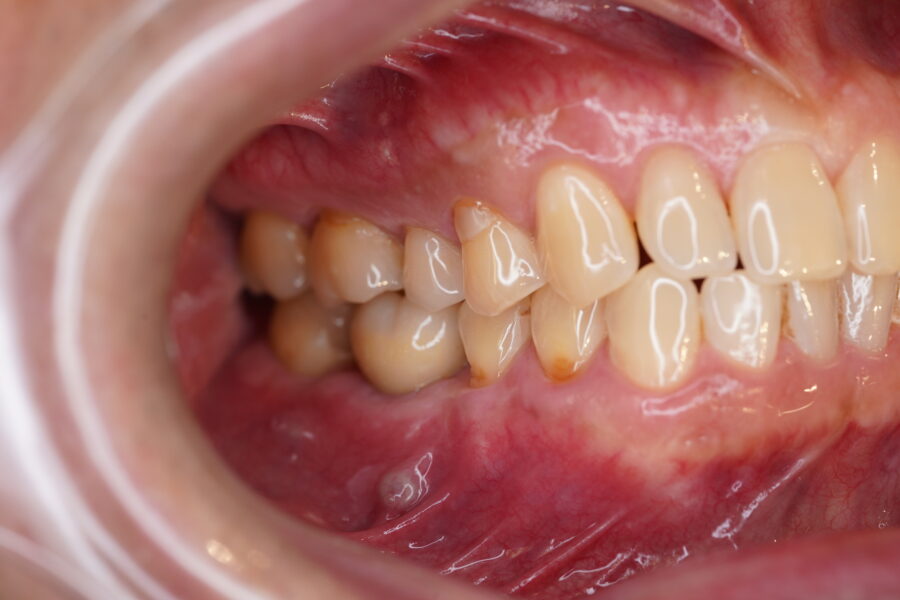

クリーニング後のお写真です![]()

プラークが付いていたところからは少し出血が見られましたが、ほぼしませんでした